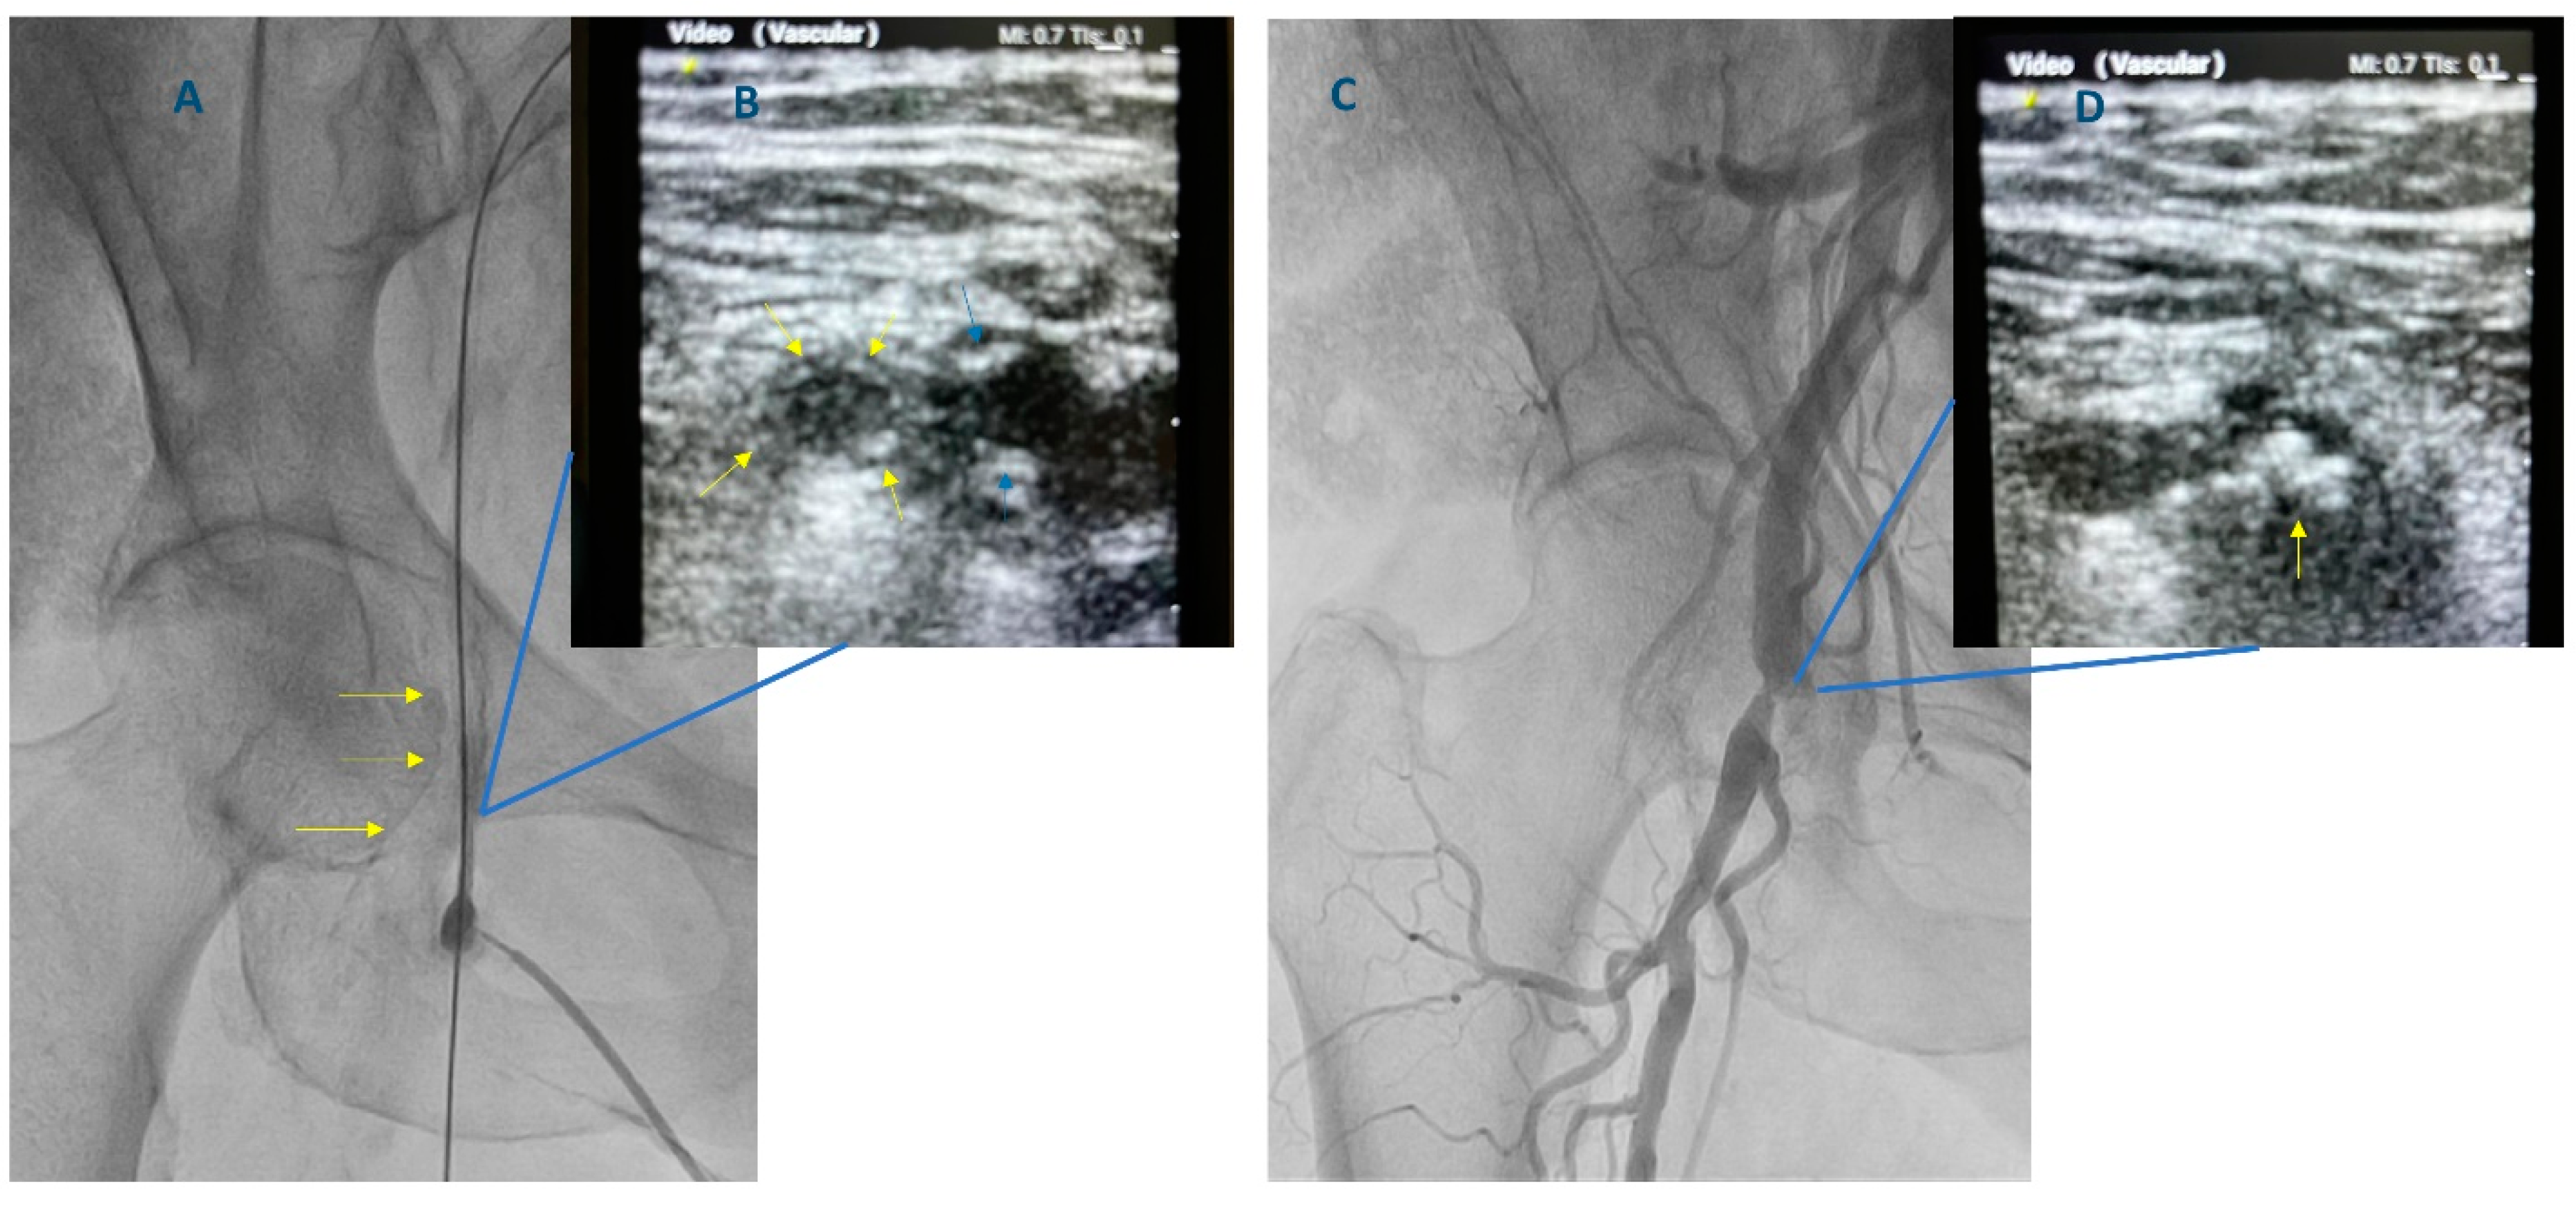

- Damluji, A.A.; Nelson, D.W.; Valgimigli, M.; Windecker, S.; Byrne, R.A.; Cohen, F.; Patel, T.; Brilakis, E.S.; Banerjee, S.; Mayol, J.; et al. Transfemoral approach for coronary angiography and intervention: A collaboration of international cardiovascular societies. JACC Cardiovasc. Interv. 2017, 10, 2269–2279. [Google Scholar] [CrossRef]

- Brilakis, E.S. Manual of Percutaneous Coronary Interventions: A Step-by-Step Approach; Elsevier/Academic Press: London, UK, 2020. [Google Scholar]

- Schnyder, G.; Sawhney, N.; Whisenant, B.; Tsimikas, S.; Turi, Z.G. Common femoral artery anatomy is influenced by demographics and comorbidity: Implications for cardiac and peripheral invasive studies. Catheter. Cardiovasc. Interv. 2001, 53, 289–295. [Google Scholar] [CrossRef]

- Sandoval, Y.; Burke, M.N.; Lobo, A.S.; Lips, D.L.; Seto, A.H.; Chavez, I.; Sorajja, P.; Abu-Fadel, M.S.; Wang, Y.; Poulouse, A.; et al. Contemporary Arterial Access in the Cardiac Catheterization Laboratory. JACC Cardiovasc. Interv. 2017, 10, 2233–2241. [Google Scholar] [CrossRef]